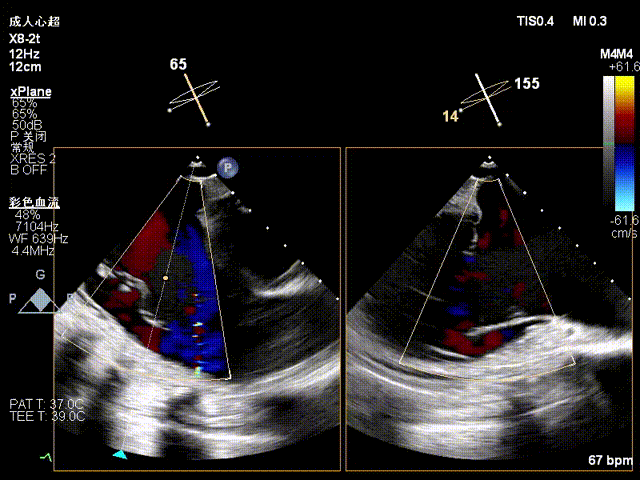

Echocardiographic findings indicated: Type IIIB quadrileaflet tricuspid malformation with extremely severe tricuspid regurgitation (5+, vena contracta: 16.1 mm on average). Regurgitant orifices were located at the anterior-septal, central, and posterior-septal regions, with a 11 mm central gap, leaflet tethering (tethering height: 10 mm), and tricuspid annular dilatation (mean annular diameter: 53 mm). The inferior vena cava diameter was approximately 25 mm, and RV FAC was 40%.

Baseline regurgitation after anesthesia

Postoperative regurgitation